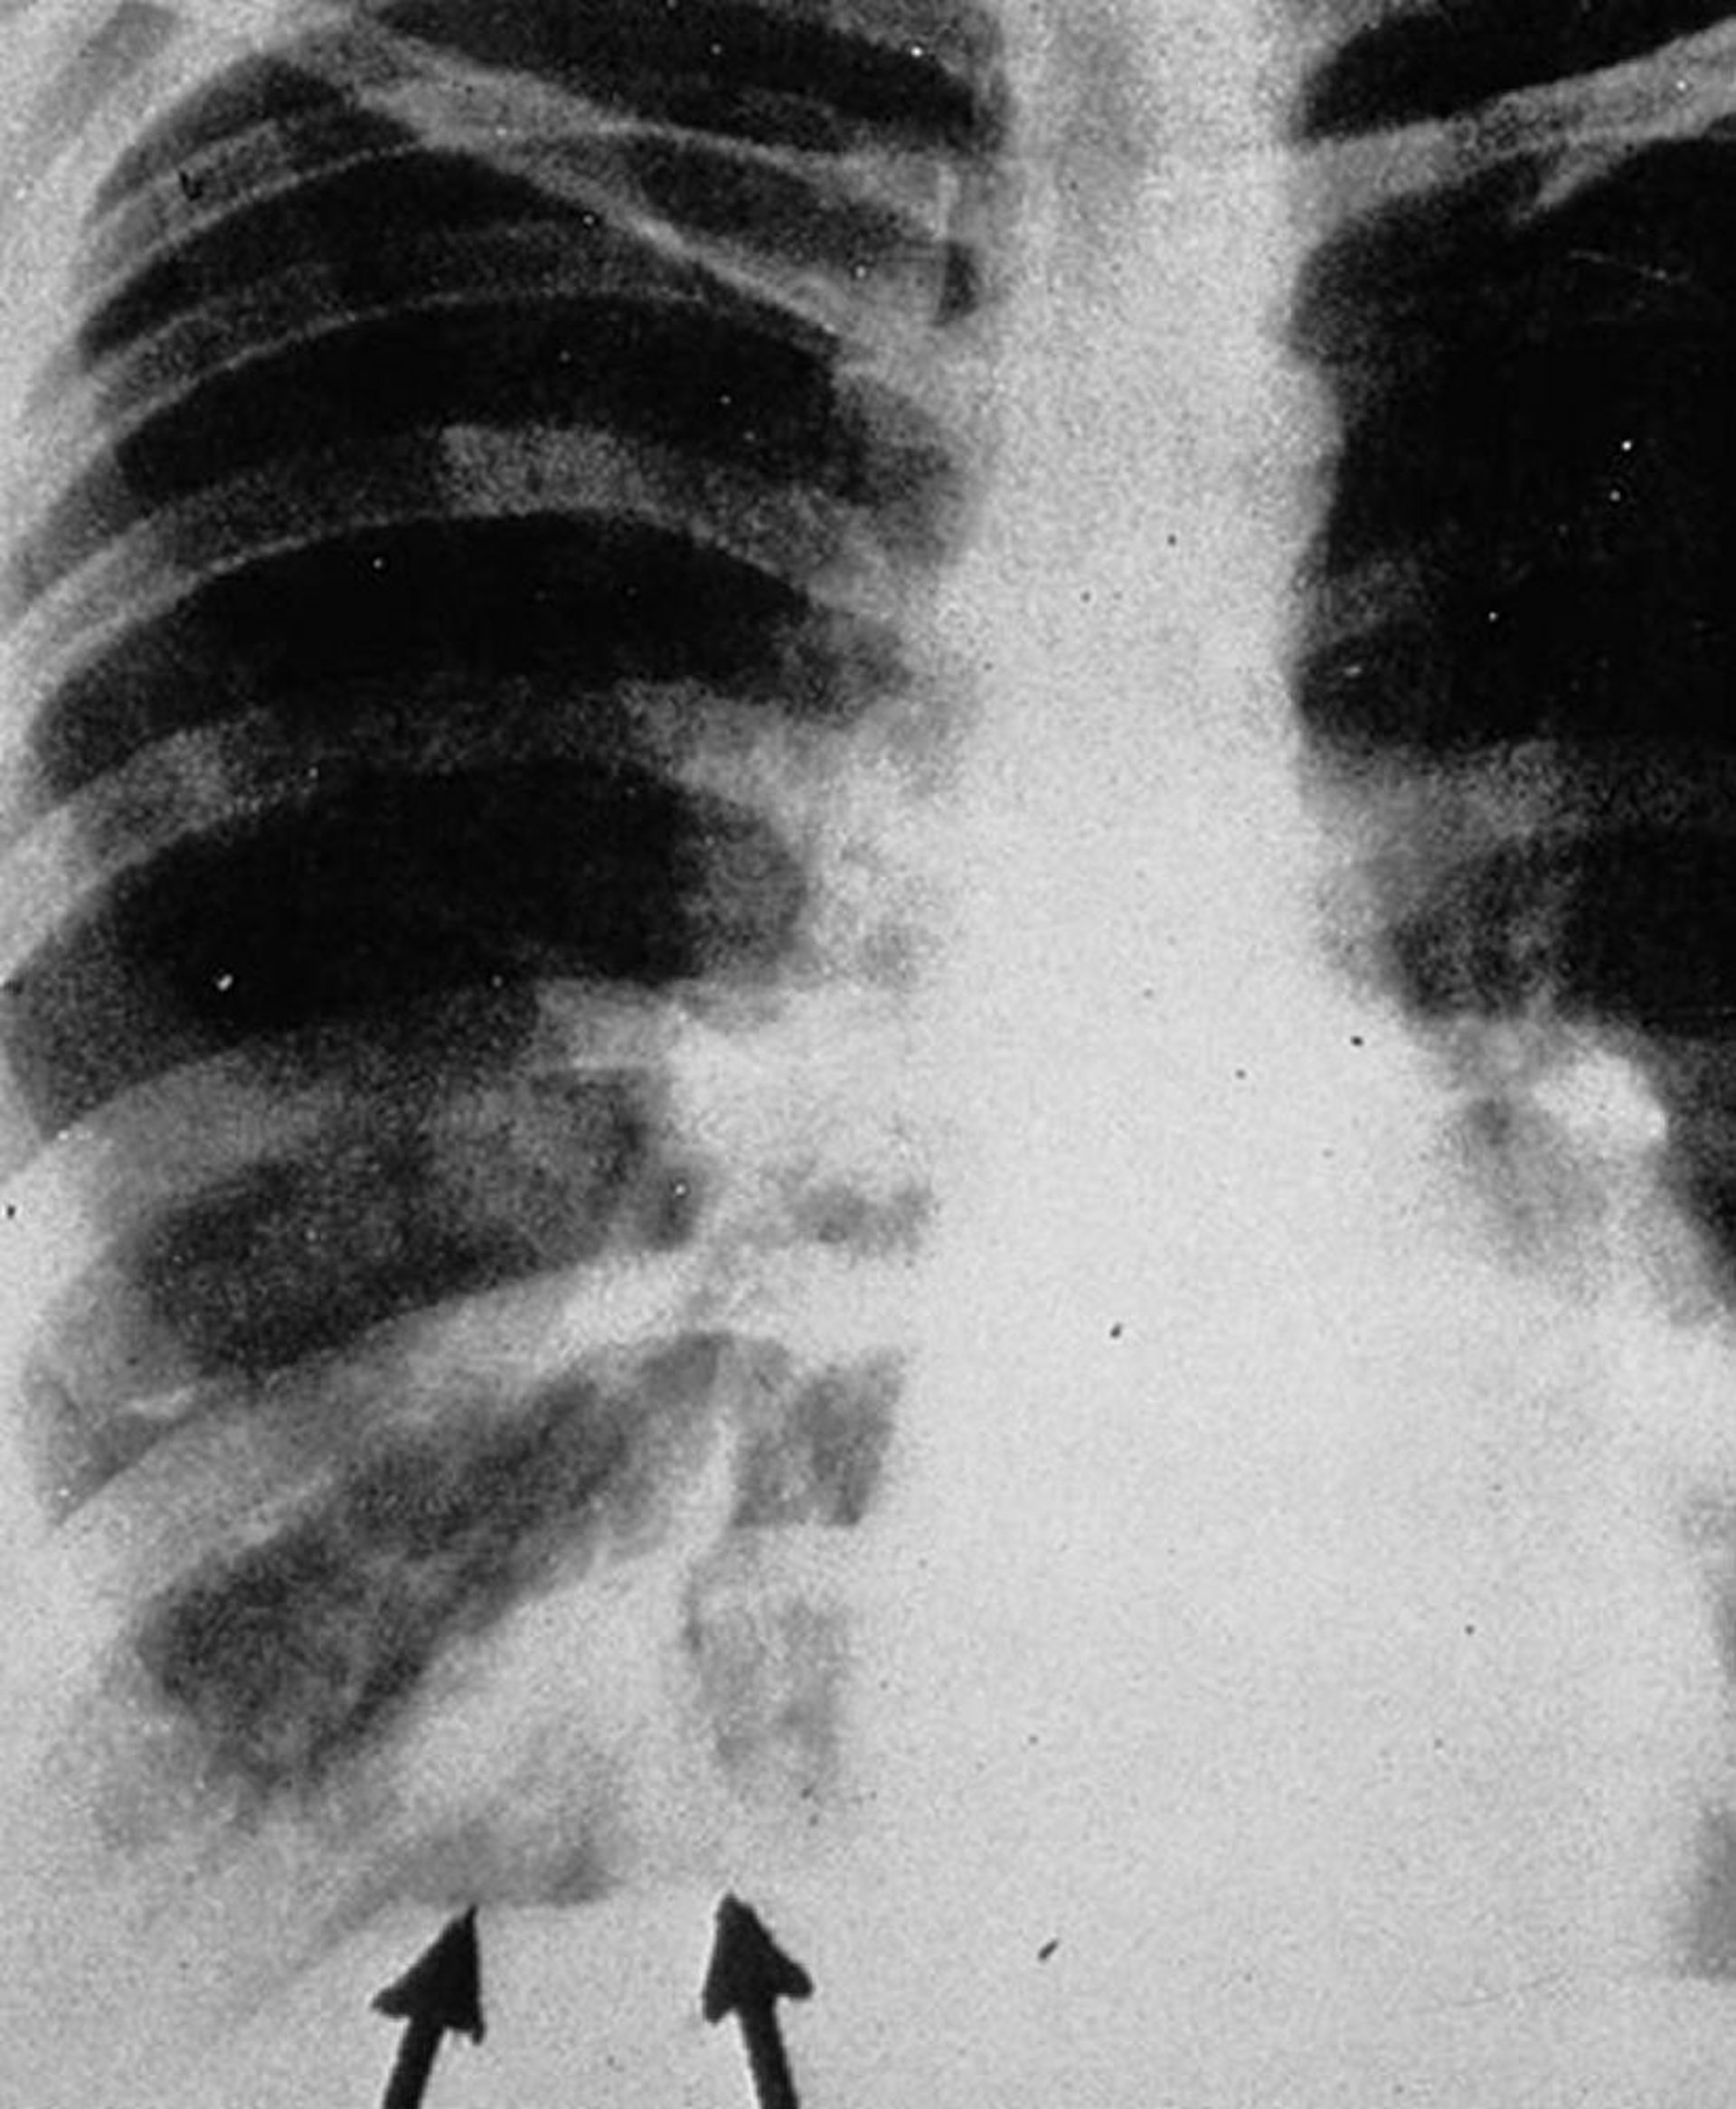

Aspergilose broncopulmonar alérgica

A radiografia póstero-anterior de tórax mostra sombras de "dedo de luva" (setas), aparecendo como densidades tubulares ramificadas que representam exsudatos intrabrônquicos com espessamento da parede brônquica.